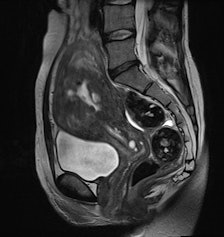

BLADE improves anatomic depiction and image quality thanks to less movement artifact, but at the expense of CNR of cystic structures or visibility of free pelvic fluid.

"From a diagnostic point of view, the distinctive MRI properties of cystic structures are of primary importance when performing female pelvic imaging," they added. "Additional use of contrast showing enhancement of solid tumor components besides including conventional non-Cartesian sampled T1- and T2-weighted images into the protocol are advocated to facilitate the diagnosis and to avoid pitfalls."

BLADE may be useful in selected cases with uterine pathologies and in cases where severe motion artifacts may be problematic using conventional T2-weighted pulse sequences. "However, due to the issues described, we would not currently recommend general replacement of conventional T2-weighted TSE sequences by BLADE in the female pelvis," the authors concluded.